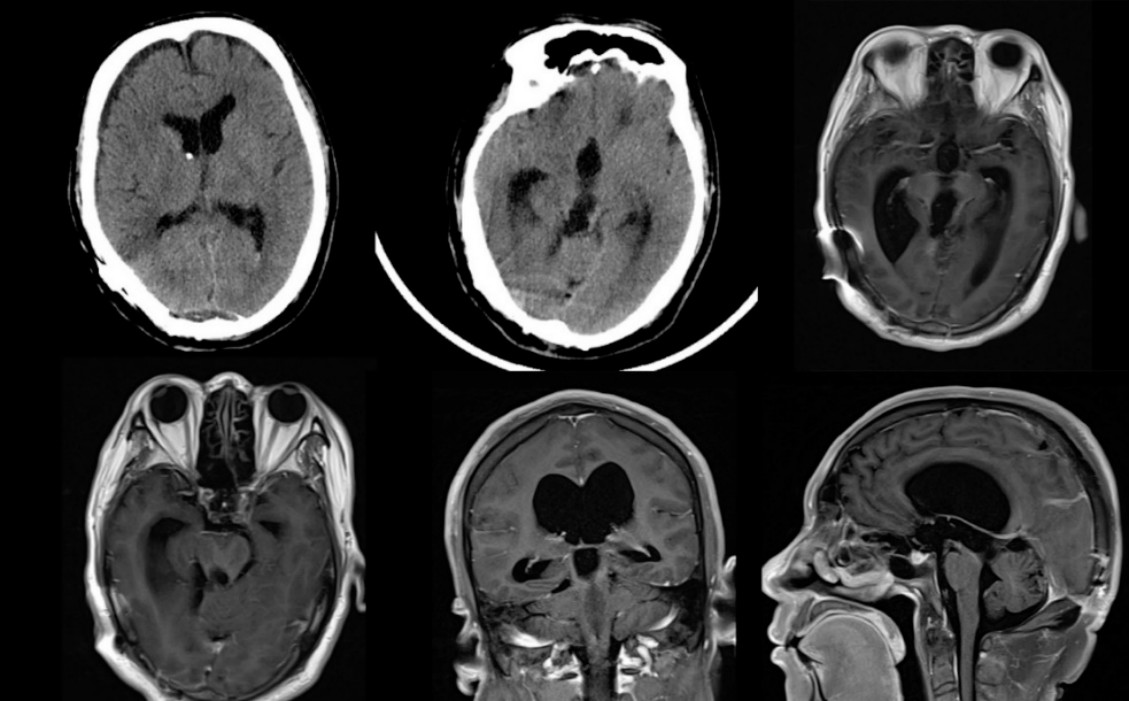

患者6年余前因“反复头部胀痛1年,加重2周”来浙医二院,查头颅CT/MRI(2013年4月)提示中脑-松果体区占位,性质?并梗阻性脑积水(图1)。腰穿测压250mmH2O,与家属沟通直接手术切除病灶及姑息分流手术减压,家属要求先行分流手术。逐行脑室-腹腔分流术,设定初始压力150mmH2O。患者术后恢复良好,症状明显好转,但术后复查头颅CT见脑积水未明显缓解,后压力逐步降至100mmH2O,多次复查头颅CT见脑积水仍基本同前。考虑患者症状已缓解,未进一步调整压力,定期门诊随访复查。

图1.头颅CT(A、B)、T2平扫(C)、T1平扫(D)、T1增强(E、F)(2013年4月)提示中脑-松果体区占位合并梗阻性脑积水,病灶无明显强化